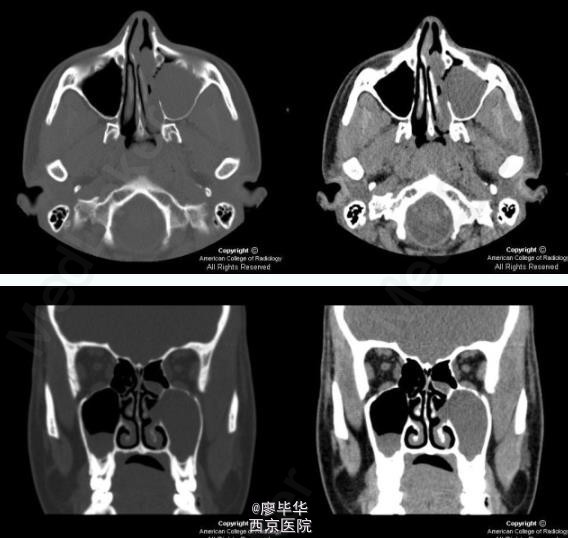

患者,20岁,女性,因有鼻塞、流脓涕并伴有头晕症状就诊。

查体可见患者有鼻塞、流脓涕并伴有头晕症状,检查可见鼻粘膜慢性充血肿胀并伴有脓性分泌物 辅查 CT

诊断;慢性副鼻窦炎来 治疗:治疗通常通过外科手术,穿刺治疗配合外用药。